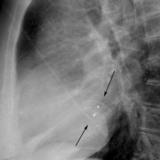

ASD 1 Lat